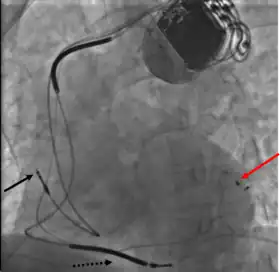

This is generally performed subsequent to RV lead placement, with the RV lead providing a backup in case of accidental damage to the electric fibers of the heart, causing an asystolic event. As with the RV lead, a guide wire is first inserted, allowing for the insertion of a multi-delivery catheter. The catheter is subsequently maneuvered to the opening of the coronary sinus in the right atrium. From here a contrast media is injected, allowing the surgical team to obtain a coronary sinus phlebogram to direct the placement of the lead into the most suitable coronary vein.[1]

Once the phlebogram has been obtained, the multi-delivery catheter is used to guide in the lead, from the chosen vein of entry, into the right atrium, through the coronary sinus and into the relevant cardiac vein.[1]

Left ventricular lead placement is the most complicated and potentially hazardous element of the operation, due to the significant variability of coronary venous structure. Alterations in heart structure, fatty deposits, valves and natural variations all cause additional complications in the process of cannulation.[1]